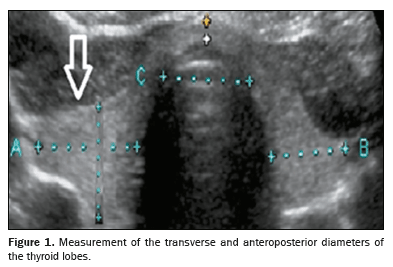

Quantitative data were extracted from archived thyroid ultrasound images. Standardized measurements included the MTLD, calculated as the average of the transverse and anteroposterior diameters of the largest lobe, as shown in Figure 1, and the TTD, the measurement of which was standardized to be performed in the transverse plane at the level of the thyroid isthmus, as illustrated in Figure 2. Despite the isthmus presenting anatomical variations, including a filiform appearance in some cases, the adopted protocol ensured image acquisition in the same anatomical plane, ensuring comparability and consistency of measurements among the cases evaluated. In addition, as depicted in Figure 3, thyroid volume was calculated directly from sonograms by using the ellipsoid formula: length × width × depth × correction factor (0.470). We also calculated the tracheal index, which is defined as the ratio between the sum of the widths of the thyroid lobes and the width of the trachea.